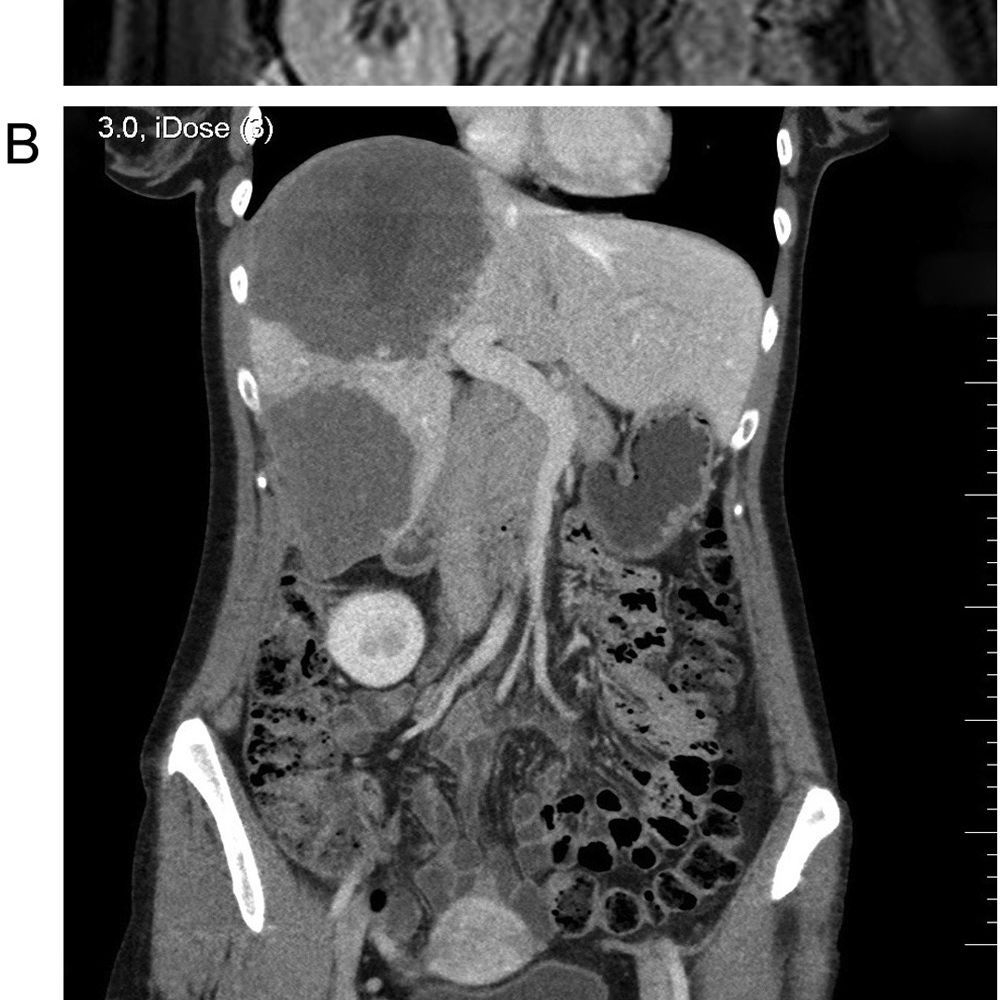

Fuchsbandwurm: Ein Parasit, der Zysten in Leber und Lunge bildet. Ohne Behandlung ist er lebensgefährlich!